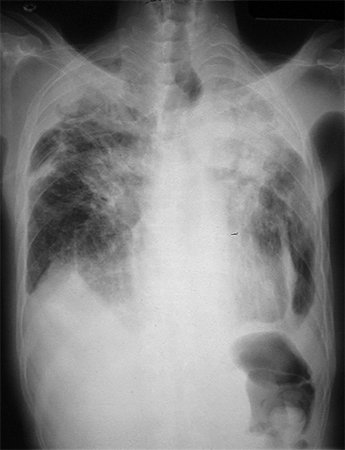

CXR of progressive massive fibrosis due to silica or coal exposure

From the personal collection of Kenneth D. Rosenman, Michigan State University